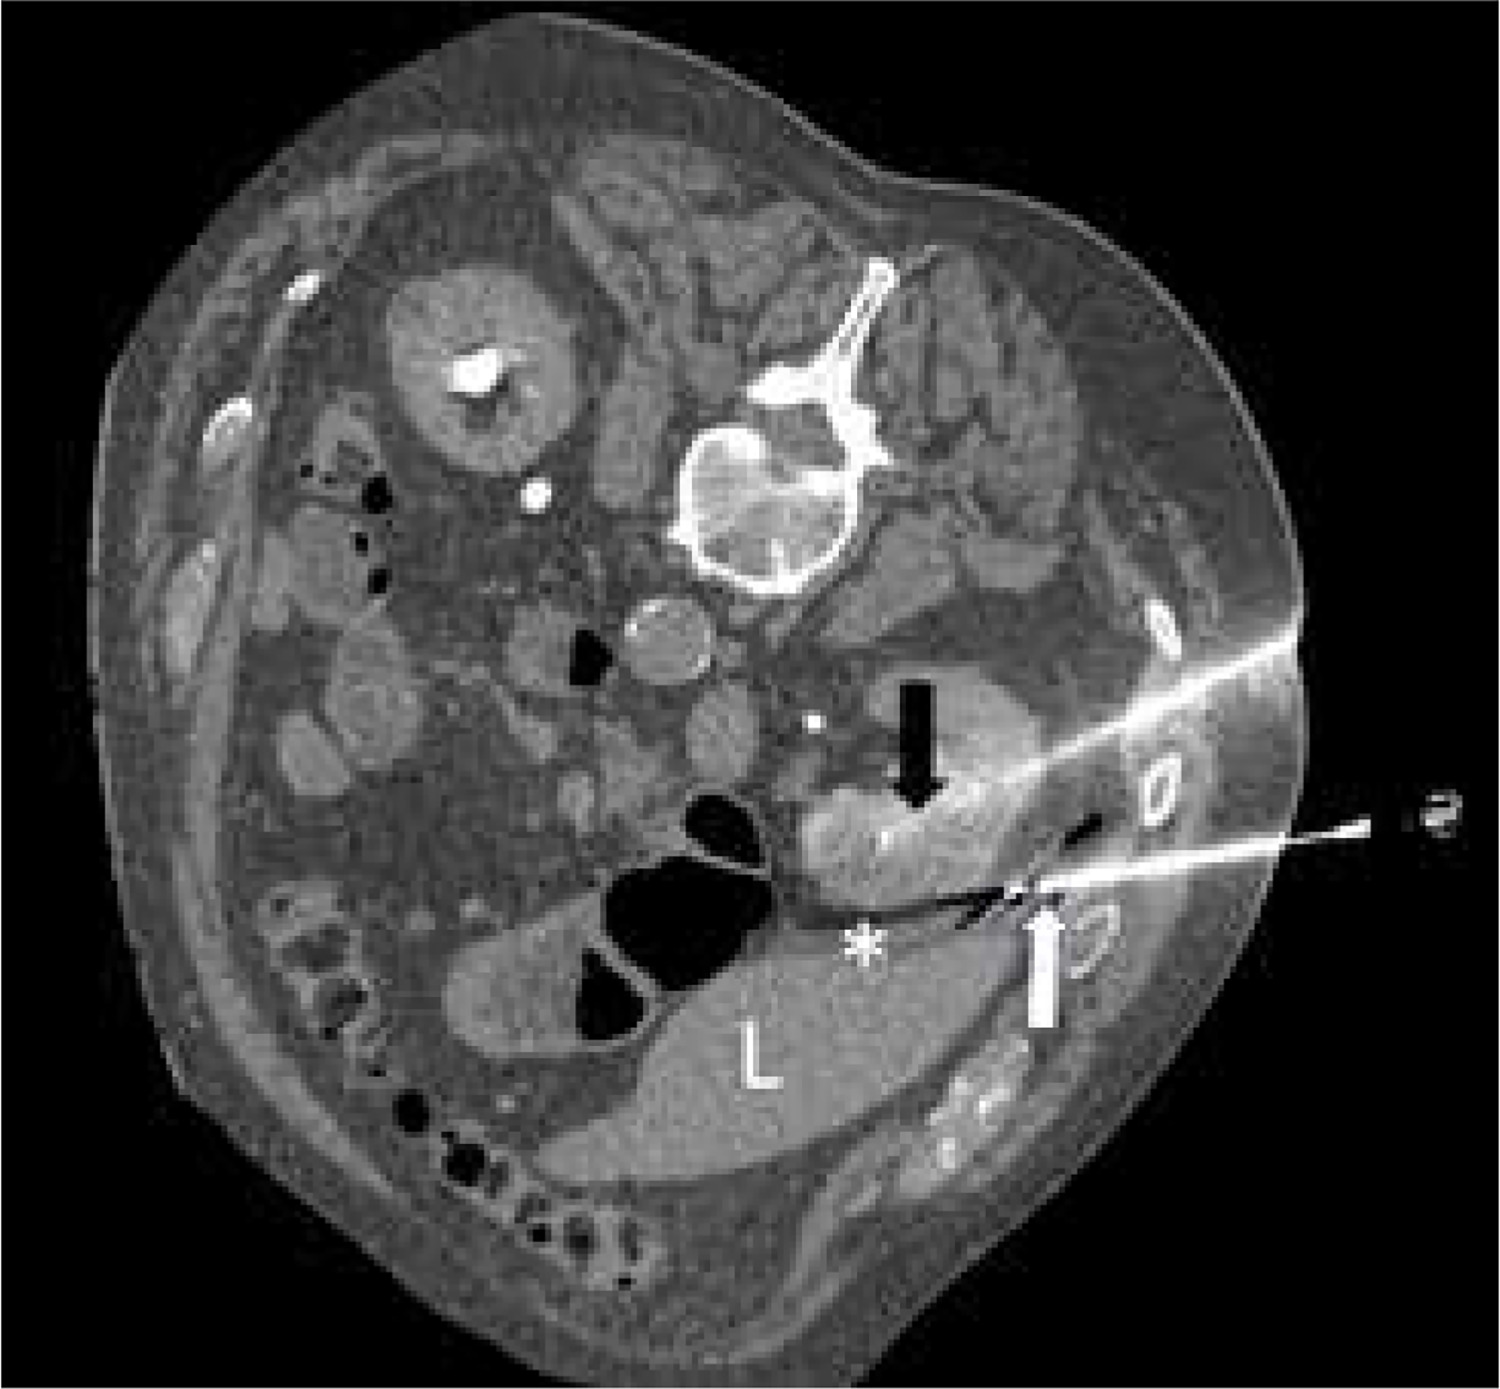

The mean number of ablation needles was 3 (range: 2-4), and it depended mostly on the size of the tumour. The needle size was 17G. In one patient, embolisation was performed before cryoablation due to high vascularity of the tumour. Hydrodissection with 100-500 ml of normal saline was carried out in 8 procedures (Figure 1).

Figure 1

Cryoablation of renal cell carcinoma. Cryoablation needle – black arrow, hydrodissection needle – white arrow, hydrodissection – asterisk, liver – L